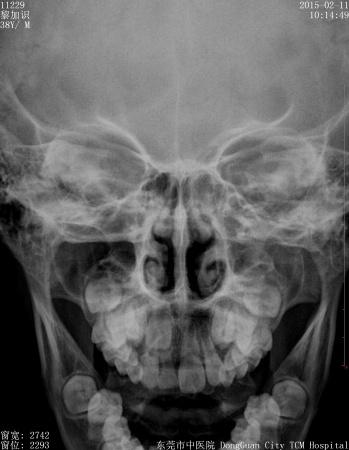

男,9岁10个月,右侧中切牙乳牙未换,右侧切牙已换。牙片显示右中切牙恒牙位置异常,与右侧切牙(恒牙)部分重叠,且右中切牙恒牙牙根稍短小(位置影响?),如何处理?能否矫正?

首先拔除乳中切牙,加强咀嚼,2、3个月后重新拍片观察情况。

最好拍个**T确定恒牙位置,确定阻生的原因,再做处理!!

乳牙拔了,,开窗助萌